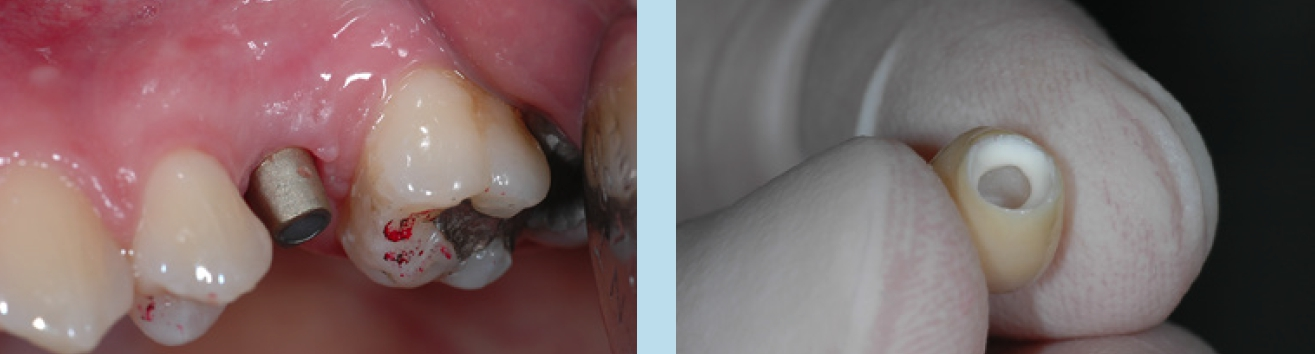

Je nach Implantathersteller stehen Gingivaformer mit unterschiedlichen Durchmessern für ein und denselben Implantatdurchmesser zur Verfügung. In der täglichen Praxis wird zu selten von dieser Möglichkeit Gebrauch gemacht, die Diskrepanz zwischen dem schmalen Diameter der Implantatschulter und dem breiteren physiologischen Durchtrittsprofil einer Molarenkrone bereits bei der Freilegung zu überbrücken.

Das Einzelimplantat anstelle einer konventionellen Brücke hat sich bewährt, da so weiterer Substanzverlust an Nachbarzähnen vermieden werden kann. Die prothetischen Komponenten bestehen bei vielen Systemen aus einem verschraubbaren Abutment und einer zementierten Krone oder aus einer direkt verschraubten Abutment-Kroneneinheit.

Bei zementierten Kronen oder Brücken wird eine mögliche Entzündungsreaktion diskutiert, die durch tief in den Sulkus verpresste und nicht entfernte Zementreste entsteht [10-12]. Diese könne zum vorzeitigen Knochenabbau führen. Direkt verschraubte Kronen oder Brücken bieten hier einen Vorteil, da kein Befestigungszement benötigt wird. Ein zusätzlicher positiver Aspekt der verschraubten Krone sind geringere Kosten im Vergleich zum individuellen Abutment mit zementierter Krone.